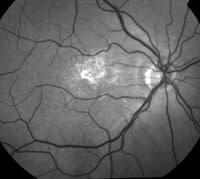

The digital color fundus image and the red-free image show fibrin and atrophic changes in this patient's macular area. |

60-year-old female with chronic central serous chorioretinopathy